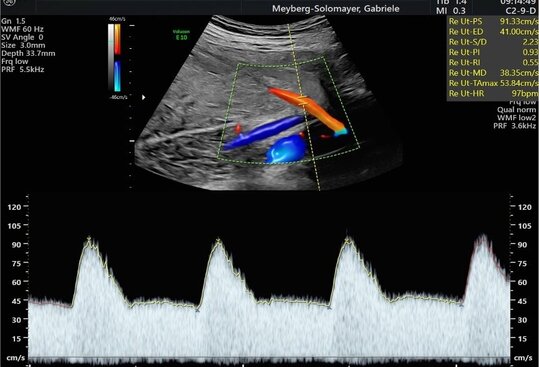

Erst-Trimester-Screening zur Risikoabklärung einer Schwangerschaftsvergiftung (Präeklampsie-Screening)

Bereits in der Frühschwangerschaft kann bei gefährdeten Patientinnen im Rahmen des Erst-Trimester-Screenings das Risiko für eine Präeklampsie (Schwangerschaftsvergiftung) abgeschätzt werden. Dies erfolgt bei uns in der Pränataldiagnostik und Schwangerenambulanz durch die Kombination aus mütterlichen Blutwerten und Dopplerultraschall (spezielle Art des Ultraschalls). Als Risikopatientinnen gelten Patientinnen, welche schon vor der Schwangerschaft einen hohen Blutdruck aufweisen oder schon einmal in der letzten Schwangerschaft an einer Schwangerschaftsvergiftung oder einem Hellp-Syndrom (schwerere Form der Präeklampsie) litten.

Ultraschalluntersuchung der mütterlichen und kindlichen Durchblutung (Farb-Dopplersonografie)

Die Durchblutung der Nabelschnur, der kindlichen Gefäße und des Mutterkuchens wird mittels einer speziellen Ultraschalltechnik durchgeführt. Mit der sogenannten (Farb-)Dopplersonografie können wir in der Pränataldiagnostik und Schwangerenambulanz die Versorgungslage überprüfen.

Auffällige Blutflussmuster können auf eine Mangelversorgung des Ungeborenen oder Auffälligkeiten im Kreislauf der Mutter hinweisen. Zu nennen wäre hier das erhöhte Risiko für einen schwangerschaftsbedingten Bluthochdruck. Mittels der Untersuchung können solche Probleme rechtzeitig erkannt und die Patientin entsprechend am UKS überwacht werden.